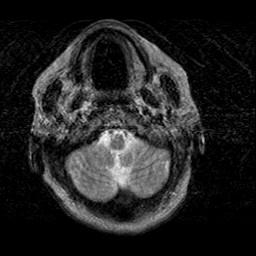

Creutzfeld-Jakob disease: T2-weighted MR -- Slice #1

[Home][Help][Clinical] Slice 1